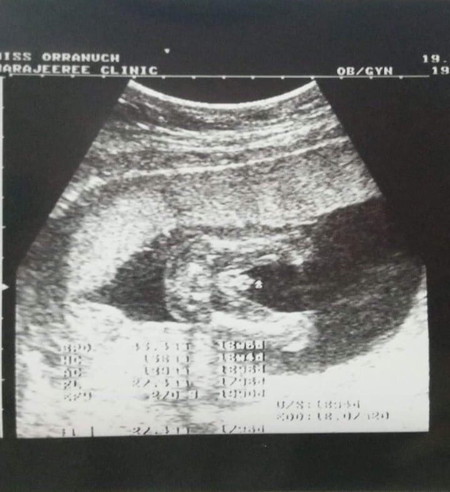

มาทายเพศกันค่ะแม่ๆ❤️?

ลองทายดูกันค่ะ ว่าแม่ได้เพศอะไร555?

ผู้ชายค่ะ ดีใจด้วยนะคะ แม่บ้านบ้านนี้อยากเห็นจู๋ชัดๆแบบนี้จังอยากได้ผู้ชายค่ะ

ของแม่ชายชัดเลยค่ะ บ้านนี้หมอก็บอกชาย100%แต่ดูไม่ออกเลยว่าตรงไหนคือจู๋

ในภาพอัลตร้าซาวเหมือนกันเลยค่ะ แต่บ้านนี้หมอบอกผู้หญิง😂

ไม่ปิดให้ทายเลยจ้ะแบบนี้ โชว์มากเลยคับลูก 👶🏻

ชัดเลยค่ะแม่ จู๋น้อยๆ เหมือนกันเลยค่ะ

จู๋โผล่ขนาดนี้ไม่ต้องทายแล้ว 😂😂